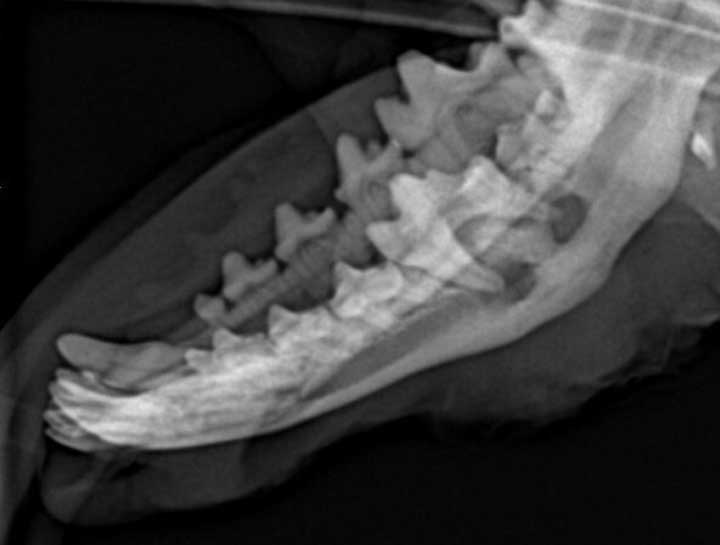

Digital Dental Radiology

Insight into underlying issues.